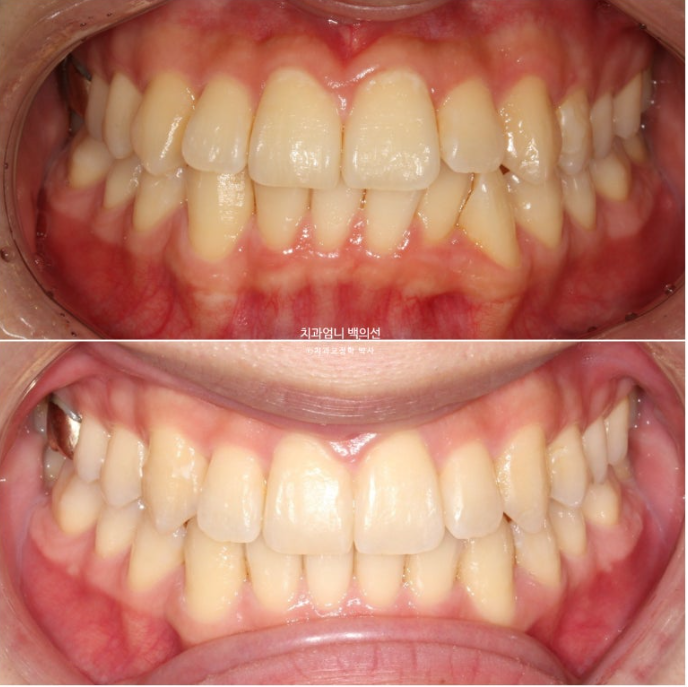

중심선 불일치가 보입니다.

골격적 비대칭은 경미하지만 앞니 중심선이 많이 달라 비대칭감을 크게 느끼고 있는 상태입니다.

앞니 중심선 불일치가 많이 좋아졌으나 아직 완벽히 맞지는 않습니다.

치료 후 중심선은 완벽하게 맞습니다.